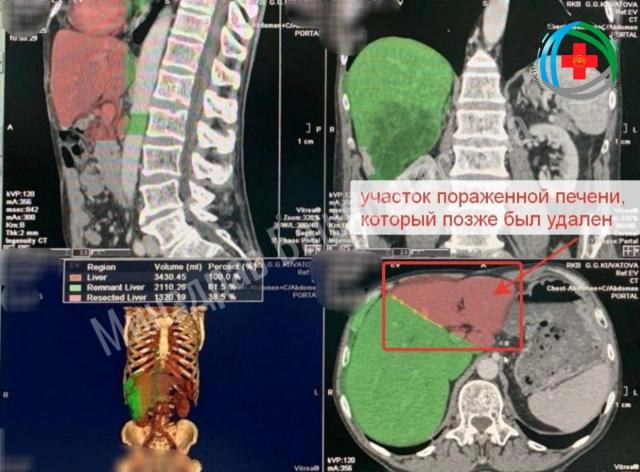

По современной методики врачи выполнили рассечение по границе долей и перевязку воротной вены, которая питала пораженную часть органов. Это помогло активному росту оставшейся здоровой части печени. Через неделю после операции функции печени нормализовались, а через 16 дней ее объем увеличился на 21,4%. После этого пораженную долю операции удалили.